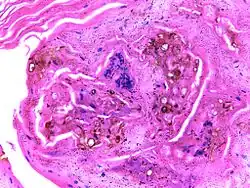

Micrograph of chromoblastomycosis showing sclerotic bodies

The most informative test is to scrape the lesion and add potassium hydroxide (KOH), then examine it under a microscope. (KOH scrapings are commonly used to examine fungal infections.) The pathognomonic finding is observing medlar bodies (also called muriform bodies or sclerotic cells). Scrapings from the lesion can also be cultured to identify the organism involved. Blood tests and imaging studies are not commonly used. On histology, chromoblastomycosis manifests as pigmented yeasts resembling "copper pennies". Special stains, such as periodic acid Schiff and Gömöri methenamine silver, can be used to demonstrate the fungal organisms if needed.